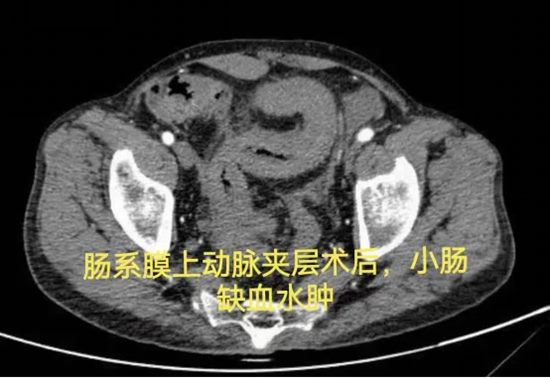

病例六:支架术后肠瘘,历经三次手术未愈,为何选择“等待”

640 (6)_副本

病情简述:53岁男性,肠系膜上动脉夹层术后出现复杂肠瘘,经历三次手术仍无法愈合,入院时白蛋白仅15.0g/L(严重营养不良)。

诊疗破局:面对再次手术的高风险,团队决定“先退一步”,将治疗重点转向营养支持。经过长达3个月的肠内联合静脉营养强化治疗,待患者身体状况改善后,再成功施行“腹腔镜肠粘连松解、瘘口小肠切除+远端回肠及回盲部结肠切除术”,最终成功康复。

技术体现:有时候,充分的术前准备与对手术时机的精准把握,比手术本身更重要。